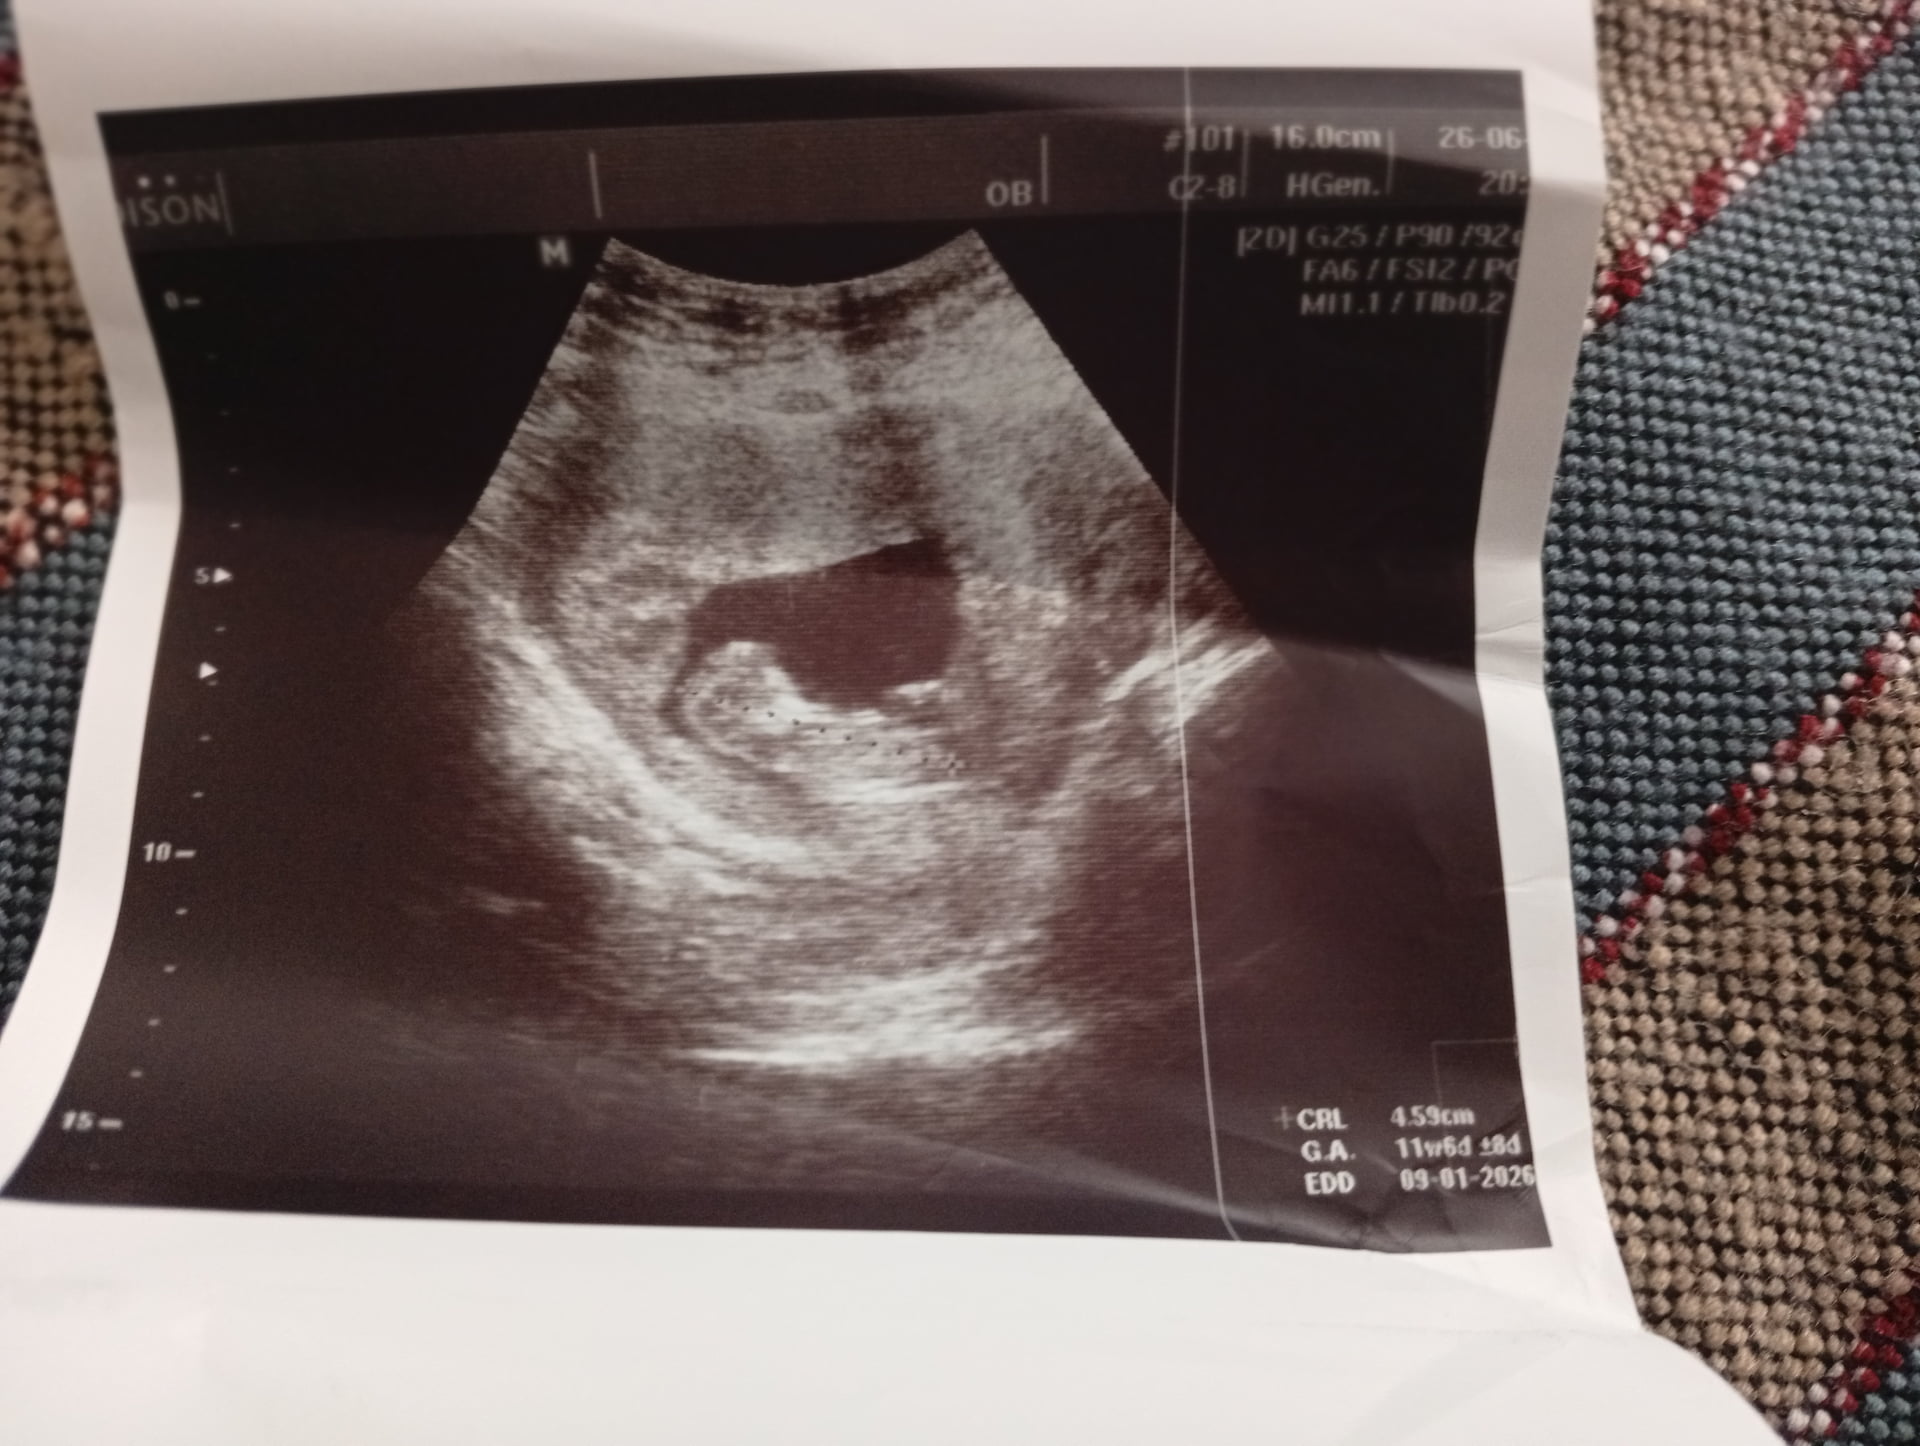

Ben kesenin fotosunu attım gözüküyor mu bilmiyorum sizce cinsiyeti bellimi

Teşekkür ederim gönlümüz kızdan yana zaten ama öncelikle saglıkla gelsin de ![]()

@Hazalikko aşko kız gibi ama uzaktan kese fotosu var mı başka acaba